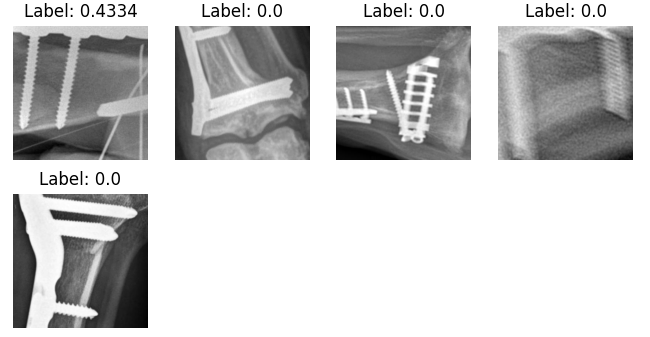

A qualitative evaluation was conducted to ascertain the practical relevance and justifiability of the mistakes made by the original production classifier. A sampling of the low SCA-value images from each cluster was reviewed by expert radiologists based on whether the highlighted regions were justifiably located for fracture assessment. Figure 4 shows an example of low-SCA crops for each cluster to illustrate this process. Note that not all clusters contain over 8 low-SCA crops for the display.

The expert radiologists provided their assessments on the nature of the mistakes and the relevance of the identified fractures. For instance, it was unanimously agreed that all the fractures identified in cluster 0 were of interest and held significant value for the business production scenario, particularly with respect to aiding accurate and trusworthy fracture diagnosis. The aberrant predictions rate was below 1% for cluster 3 and below 5% for clusters 2 and 5. Clusters 4 and 1 contain most of the aberrant predictions with 81% for cluster 4 and 25% for cluster 1.